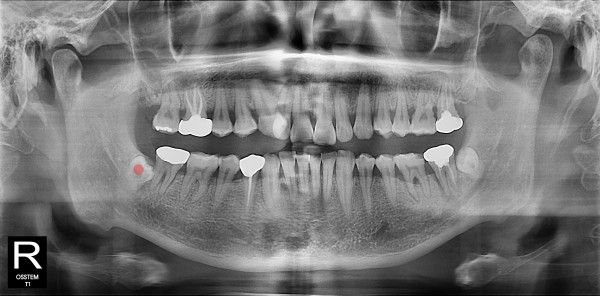

사랑니발치 30대/남성

5e20e086184bc11a2d853605b7813944_1764319927_6616.jpg